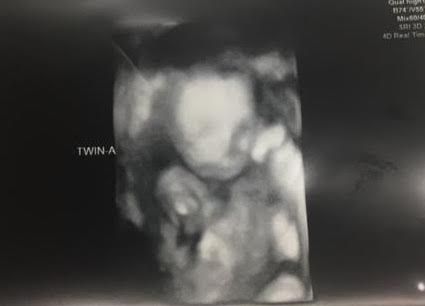

Ultrasound Photos at 21 Weeks Pregnant With Twins